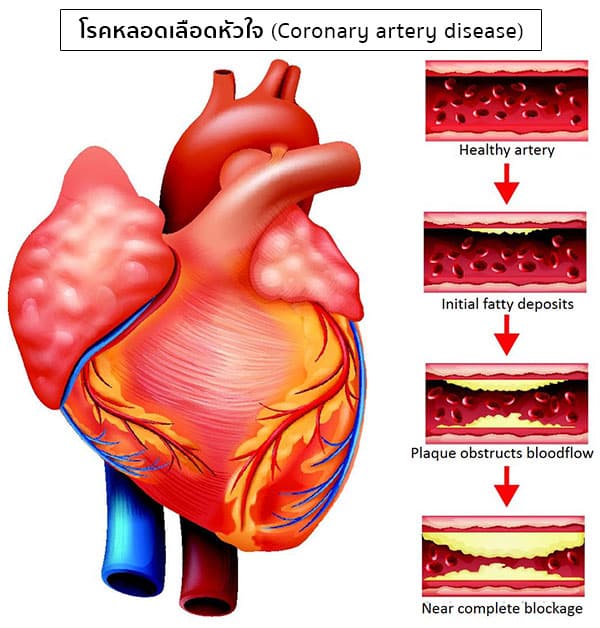

เอกซเรย์กระดูกโคนขา ภาพสต็อก – ดาวน์โหลดรูปภาพตอนนี้ – สะโพก – ส่วนของ … โรคหลอดเลือดหัวใจ (Coronary artery disease) อาการ สาเหตุ การรักษา ฯลฯ

โรคหลอดเลือดหัวใจ (Coronary artery disease) อาการ สาเหตุ การรักษา ฯลฯ หมอเอ็กโซติกอ่านฟิล์ม “การเอกซเรย์และ ECG ในกระต่ายหัวใจโต” – epofclinic